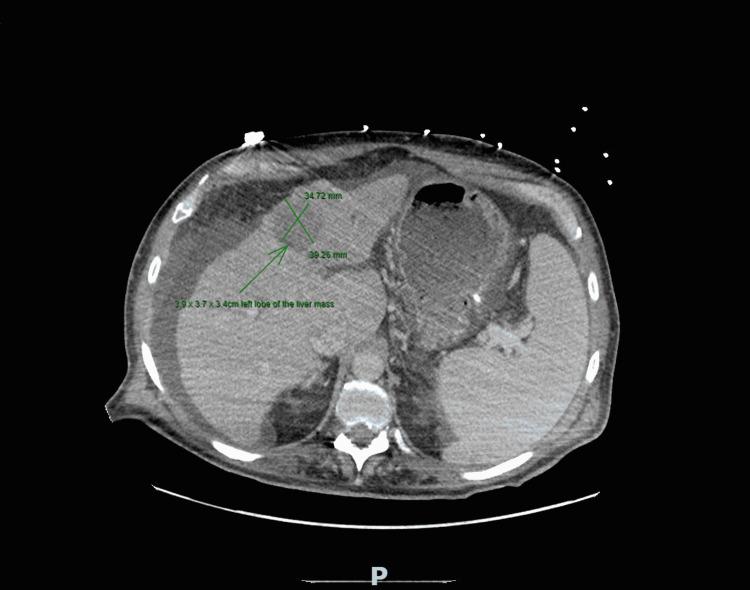

Hepatocellular carcinoma (HCC) is a common form of cancer and the most common form of liver cancer. Multiple etiological factors leading to HCC include hepatitis B and C, diabetes, alcoholic fatty liver disease, and non-alcoholic fatty liver disease. Hepatocellular carcinoma in the late stages may present with tumor burden and thrombi that can extend into the right atrium (RA). This late-stage form of HCC has a poor prognosis. In this case, we present a 63-year-old male who presented to the hospital with acute encephalopathy with bilateral pulmonary emboli and a thrombus secondary to HCC extending into the RA. Clinical trials for non-surgical interventions are ongoing and are needed to treat patients with tumor burden who may be at bleeding risk from tumor resection.

肝细胞癌(HCC)是一种常见的癌症形式,也是最常见的肝癌类型。导致HCC的多种病因包括乙型和丙型肝炎、糖尿病、酒精性脂肪肝病和非酒精性脂肪肝病。晚期肝细胞癌可能出现肿瘤负荷和血栓,血栓可延伸至右心房(RA)。这种晚期HCC预后较差。在此病例中,我们报告一名63岁男性,因急性脑病伴双侧肺栓塞以及继发于HCC的血栓延伸至RA而入院。针对非手术干预的临床试验正在进行,对于有肿瘤负荷且可能因肿瘤切除而有出血风险的患者,需要进行此类试验来进行治疗。